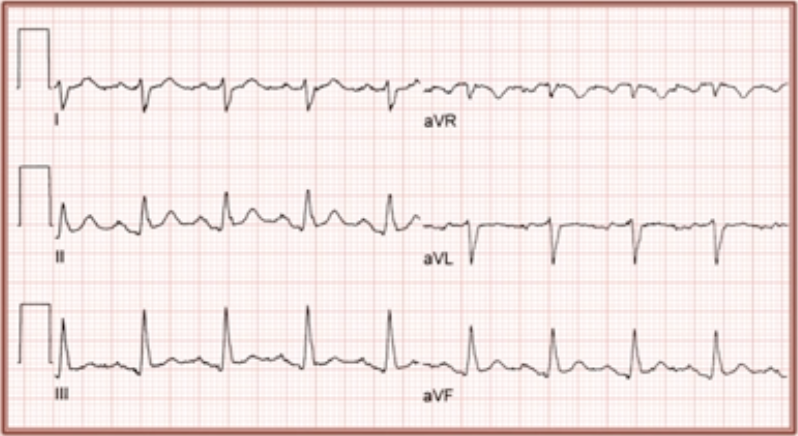

LBBB

* Broad R wave and deeply inverted T waves in lead I, aVL and V6

* Deep S wave and ST elevation and prominent T wave in V1-V3